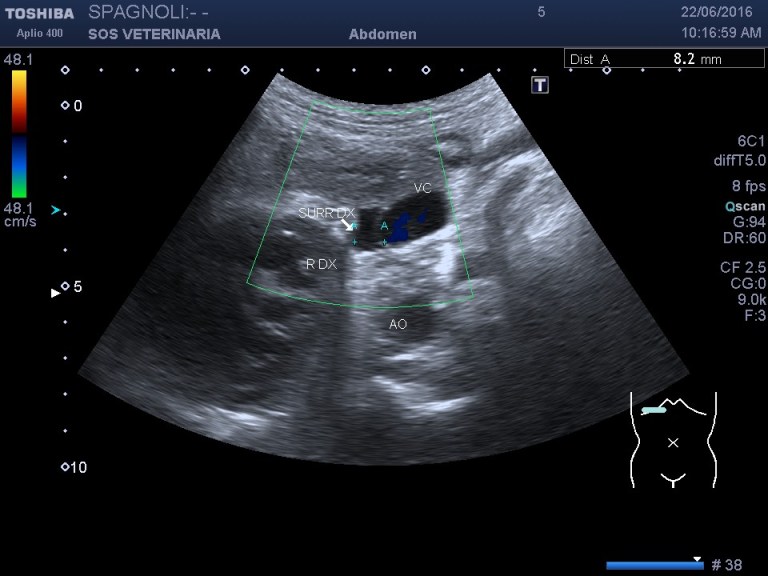

Esame ecografico.

evidente iperplasia ,morfologia conservata

nella destra asse lungo i valori superano di poco il riferimento

anche in asse corto si supera il valore di riferimento